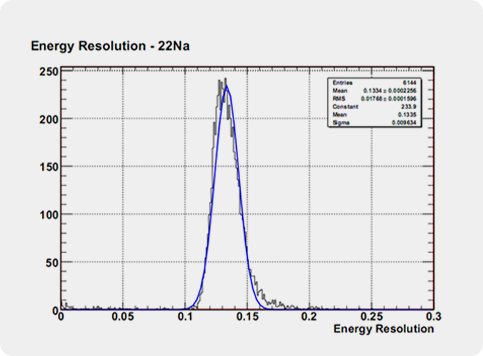

The main spectroscopic characteristics of the Clear-PEM system are energy resolution for 511 keV photons of of 13.4%, coincidence time resolution of 2.8 ns (FWHM) and DoI resolution of 2.8 mm (FWHM).